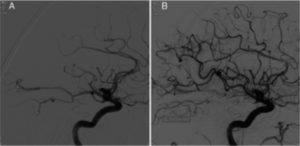

Thrombectomy for M2 occlusions

Many trials show that endovascular therapy (EVT) works to treat occlusions of the internal carotid artery or the M1 branch of the middle cerebral artery (MCA). AHA Guidelines suggest it might be reasonable to consider emergent EVT on more distal occlusions like M2 and M3 branch occlusions of the MCA. The Trevo Registry shows us that in real world practice, 23% of all thrombectomies are done for patents with M2 MCA occlusions. The figure shows restored blood flow in one such M2 occlusion before (A) and after (B) EVT.